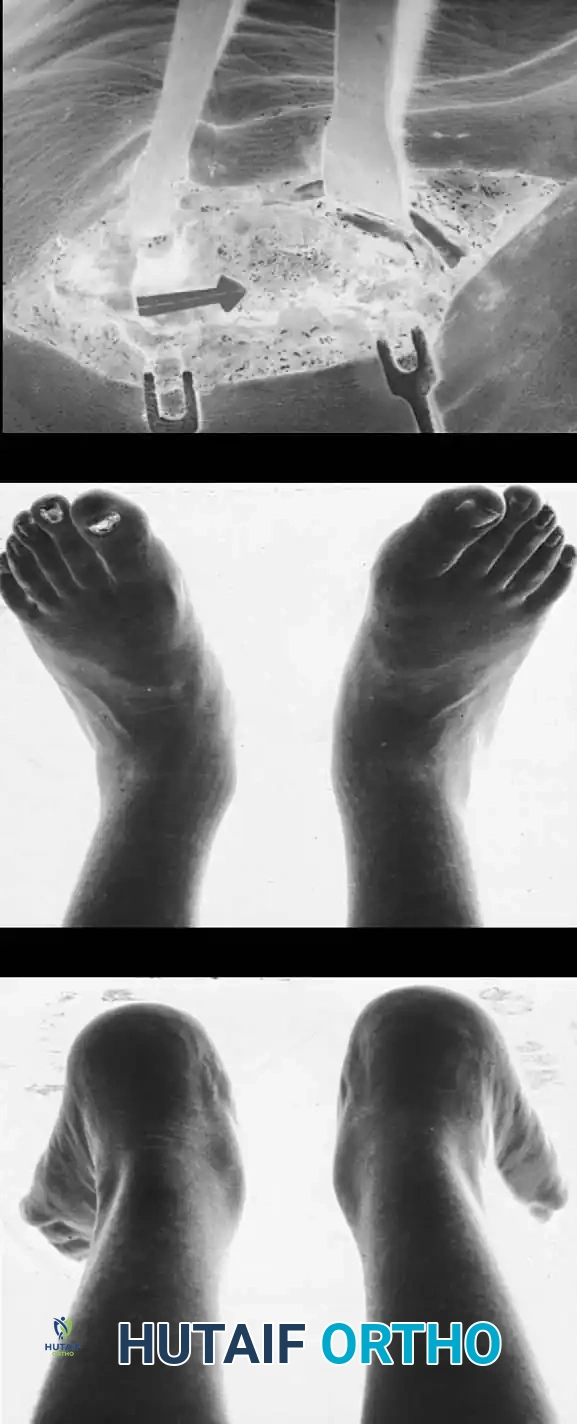

🔪 Surgical Technique 79-6: The Kidner Procedure

1. Incision and Exposure

-

Incision: Begin the skin incision 1 to 1.5 cm inferior and distal to the tip of the medial malleolus. Arch the incision slightly dorsalward, peaking directly over the medial prominence of the accessory navicular, and slope it distally to the base of the first metatarsal.

-

Dissection: Carefully dissect through the subcutaneous tissues. Identify and ligate the plantar communicating branches of the saphenous venous system. Protect the terminal branches of the saphenous nerve.

-

Tendon Identification: Identify the posterior tibial tendon as it approaches the accessory navicular.

-

Tendon Exposure: Identify the dorsal and plantar margins of the PTT approximately 2 cm proximal to the accessory navicular. Expose the tendon distally, ending at the bone.

Surgical Warning: It is imperative to expose the entire tendon without disturbing the portion extending plantarward toward its multiple insertions on the cuneiforms and metatarsal bases. Preserving these plantar slips maintains the structural integrity of the midfoot.

2. Transposition and Advancement of the PTT

-

Ossicle Excision: Using sharp dissection, meticulously shell the accessory navicular out from the substance of the posterior tibial tendon. If transposition of the tendon is planned, attempt to leave a microscopic sliver of bone within the tendon to enhance subsequent bone-to-tendon healing.

-

Navicular Resection: Resect the medial prominence of the main navicular so that it is flush with the medial border of the first cuneiform. This is typically achieved using an osteotome, followed by a rongeur and rasp to smooth the cortical edges.

-

Tendon Advancement: Suture the PTT to the apex of the medial longitudinal arch. This can be achieved by utilizing local periosteum and ligamentous tissue to secure the transposed tendon slip, or by passing heavy non-absorbable sutures through drill holes placed in the center of the navicular and tying them dorsally.

- Biomechanical Reduction: Try to advance this slip of tendon while the talonavicular joint is anatomically reduced. Reestablish the medial longitudinal arch by holding the midfoot and forefoot in a cavovarus position during knot tying.

3. Skin Closure and Casting

- Closure: Close the subcutaneous tissue and skin with absorbable sutures or adhesive skin strips. A meticulous closure is required as the postoperative cast will remain in place for an extended period.

- Immobilization: Apply a long leg, bent-knee cast in two parts. Ensure the cast is well-padded and gently molded into the longitudinal arch with the talonavicular joint reduced and the foot inverted. The knee should be flexed to 45 degrees to relax the gastrocnemius.

- Alternative Protocol: If the patient is highly reliable and the parents are thoroughly informed, a short leg non-weight-bearing cast with the foot in equinovarus is a reasonable alternative. The cast must remain in place for 4 weeks.

Advanced Imaging and Anatomical Reference Gallery

The following images illustrate various presentations, surgical exposures, and advanced imaging modalities (including CT and MRI correlates) utilized in the comprehensive evaluation and treatment of rigid pes planus and tarsal coalitions: